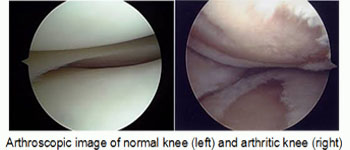

Arthroscopy. During arthroscopy, doctors use small incisions and thin instruments to diagnose and treat joint problems. This usually involves two or three puncture holes made over the knee joint and is a minimally invasive surgery. It is most often performed as a day care surgery.

In osteoarthritis, the cartilage in the knee joint gradually wears away. As the cartilage wears away, it becomes frayed and rough, and the protective space between the bones decreases. This can result in bone rubbing on bone, and hence cause pain.